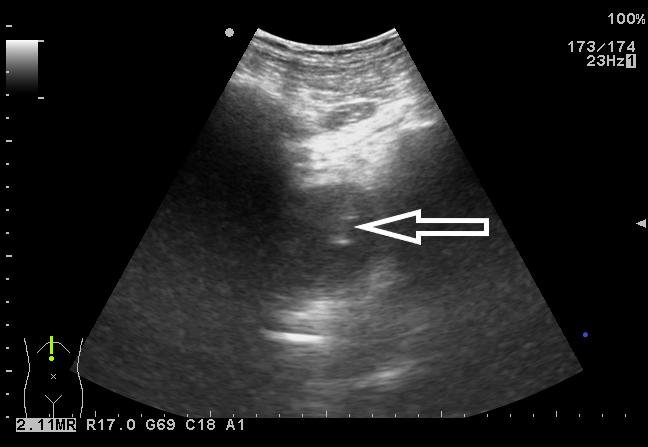

患者入院后完善相关检查,血常规:白细胞6.73×109/L,中性粒细胞4.87×109/L,血小板126×109/L;C-反应蛋白 > 90 mg/L;降钙素原7.6 ng/mL;凝血功能:PT 15 s。盆腔超声显示:骶前间隙可见一80 mm×46 mm的无回声区,内可见斑点样中强回声(图 2)。排除禁忌后,于入院当晚行超声引导下穿刺置管引流术,由于脓肿位置较深,经腹途径有肠管﹑膀胱和直肠的遮挡,所以本中心决定选择超声引导下经臀穿刺引流术。

|

| 图 2 盆腔超声显示:骶前间隙可见一80 mm×46 mm的无回声区,内可见斑点样中强回声 |